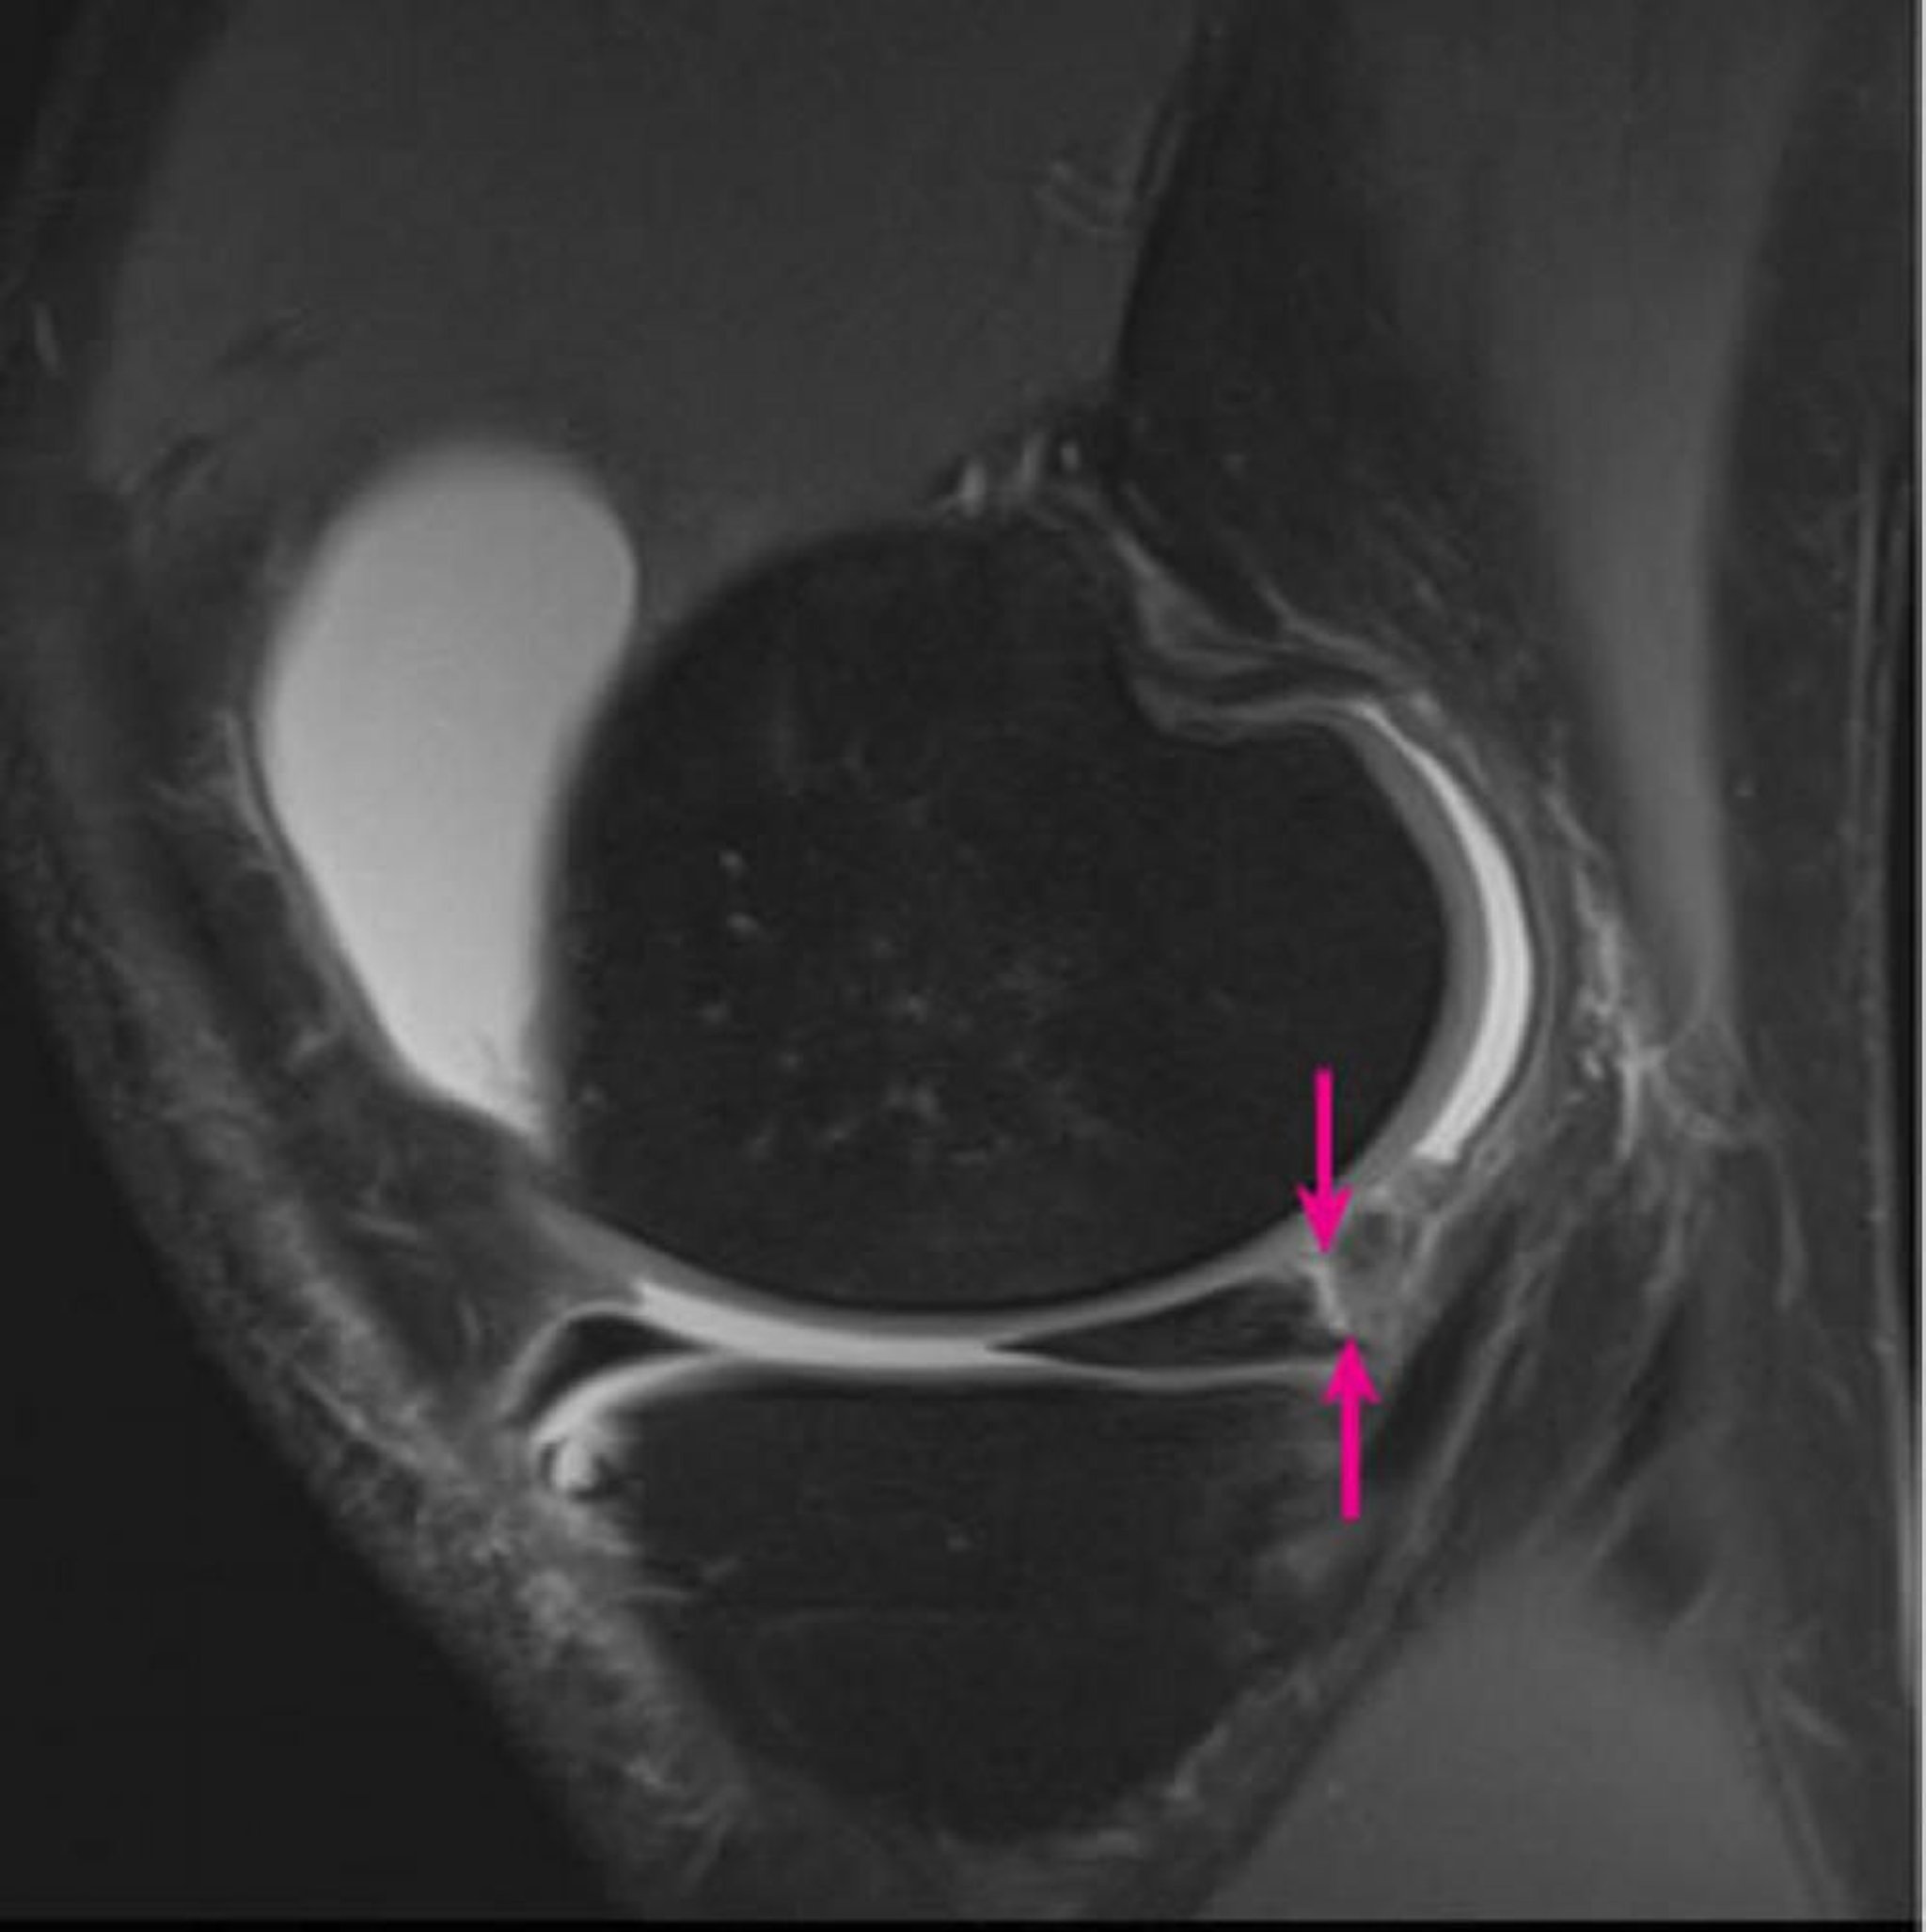

L'imagerie par résonance magnétique 3 Tesla sagittale pondérée en densité de protons du genou droit montre une séparation méniscocapsulaire impliquant la corne postérieure du ménisque médial (flèches) et un grand épanchement articulaire du genou (blanc).

Image courtoisie de Hakan Ilaslan, MD.